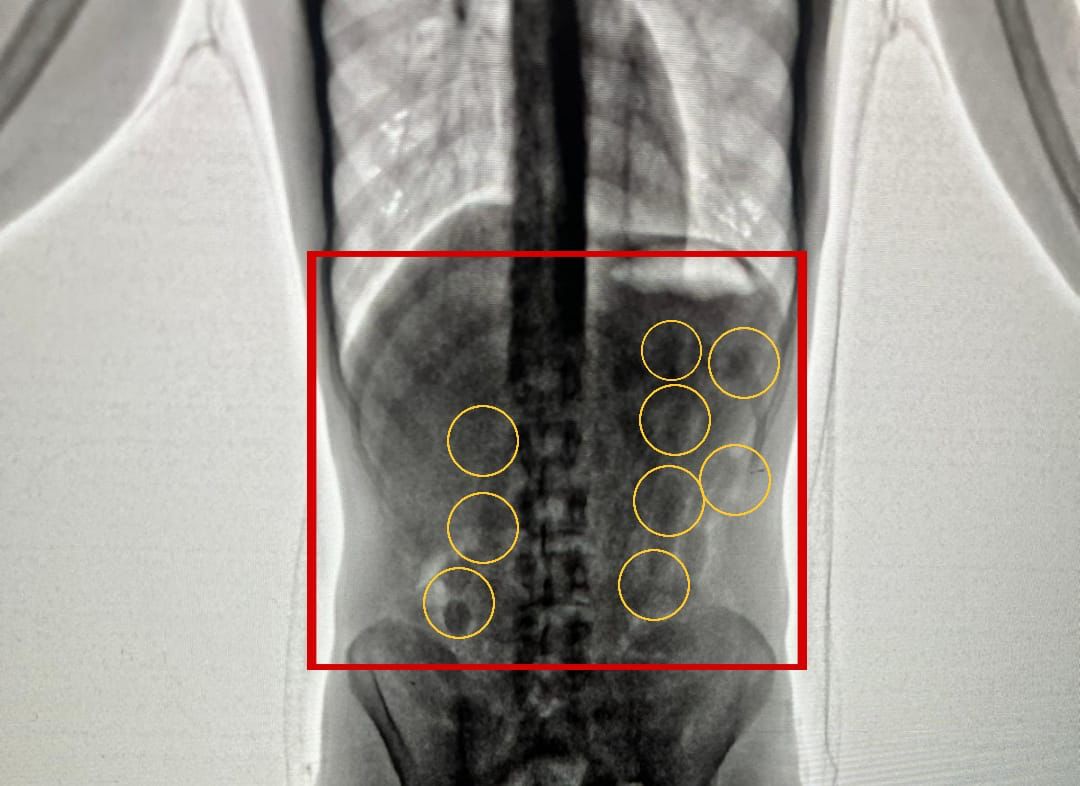

بين الناطق الاعلامي باسم مديرية الأمن العام أن كوادر إدارة مكافحة المخدرات أحبطت في مطار الملكة علياء الدولي محاولة تهريب 2 كغم من مادة الكوكايين المخدرة داخل أحشاء شخصين من جنسية أجنبية. وفي التفاصيل قال الناطق الإعلامي أن إدارة مكافحة المخدرات تابعت معلومات توافرت لديها حول نية أجنبيين قادمين عبر مطار الملكة علياء الدولي تهريب كمية كبيرة من المواد المخدرة ، إذ حُدد موعد وصول المشتبه بهما وأُلقي القبض عليهما فور محاولتهما دخول المملكة . وبعد تفتيشهما والكشف عليهما بواسطة الاجهزة اللازمة اكتُشف وجود كميات من المواد المخدرة داخل أحشائهما ، وجرى إخراج هذه المواد بالطرق الطبية، وقُدرت ب 2 كغم من مادة الكوكايين المخدرة . وأكد الناطق الإعلامي انه وبمتابعة التحقيق حُددت هوية الشخص المستلم للمواد المخدرة داخل المملكة وهو من جنسية عربية وأُلقي القبض عليه وأودعت القضية لدى مدعي عام محكمة امن الدولة . وشدّد الناطق الإعلامي لمديرية الأمن العام، أن مديرية الأمن العام لم ولن تتهاون مع أية محاولة لتهريب أو إدخال هذه السموم إلى الأراضي الاردنية، وتسخر لهذا الواجب إمكاناتها وقدراتها الفنية والاستخبارية كافة، وستضرب بقوة على كل من تسول له نفسه الخروج عن القوانين وافساد المجتمع بهذه الآفة. |